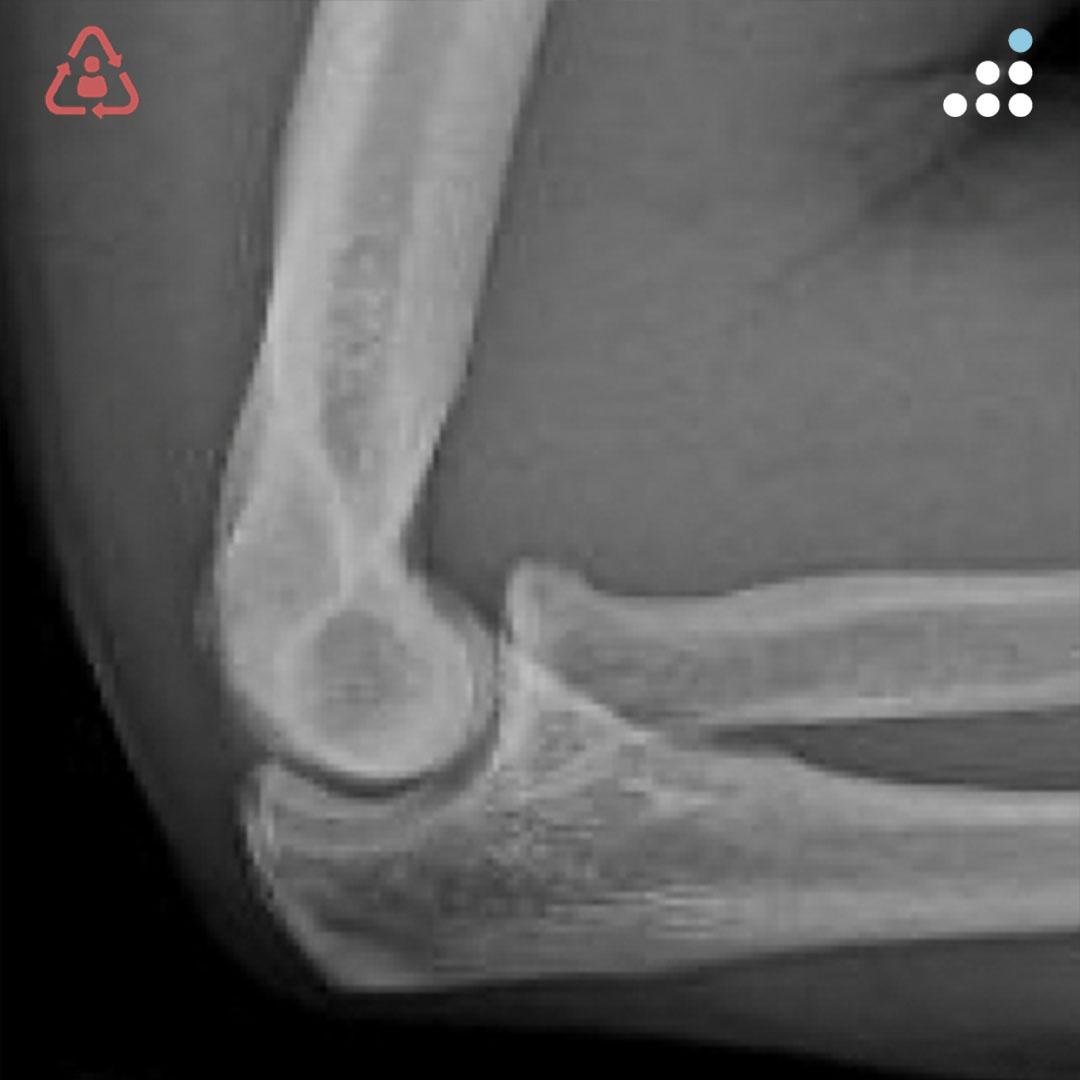

@orthobullets @KPSCALnews @rkh_md @DrMarecek @DeformityDoc @jamesablairMD @FractureDoc @stevemchale @traumaticum @DrFraneNicholas I am concerned about the +Fleck/flake sign. Get MRI or ultrasound to rule out a triceps rupture. If torn, I would perform ORIF and Triceps repair, after restoring the underlying metabolic issues. If the triceps is not torn, then would treat non-operatively.